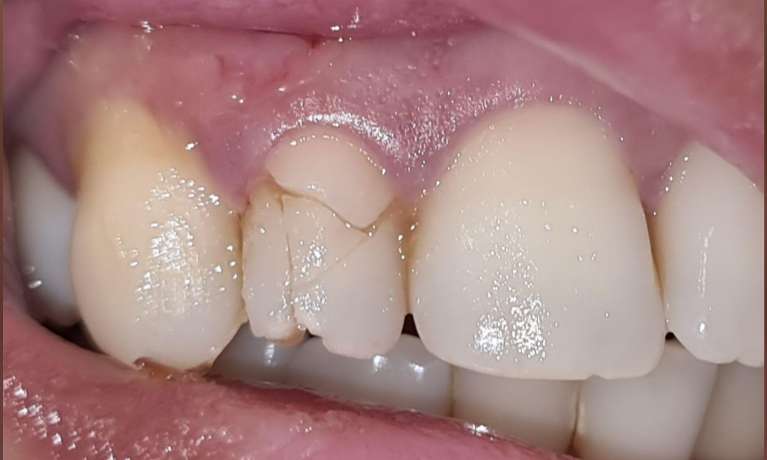

This case showcases the successful outcome of a gum graft procedure performed around an existing dental implant. Initially, the patient experienced gum recession around their implant, which can sometimes expose the implant's margin or simply lead to an uneven gum line.